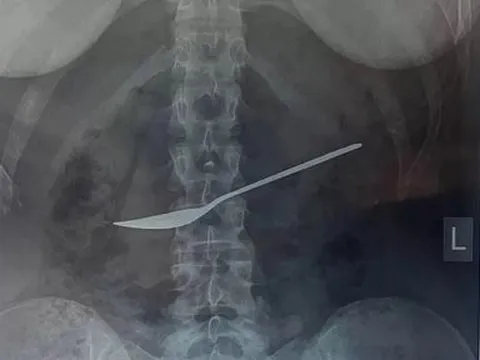

Đau bụng nhập viện, bác sĩ sốc nặng khi lấy ra thứ trong bụng cô gái

Các bác sĩ choáng váng đã lấy một chiếc thìa kim loại có kích thước 20 cm ra khỏi dạ dày của một cô gái sau khi cô nuốt nó trong lúc ăn trưa.